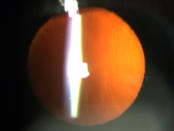

Eine Katarakt (links) verursacht ein unscharfes Bild durch vermehrte Lichtstreuung. Ein Linsen - tausch (rechts) korrigiert den Abbildungsfehler.

Eine Katarakt (links) verursacht ein unscharfes Bild durch vermehrte Lichtstreuung. Ein Linsentausch (rechts)  korrigiert den Abbildungsfehler.